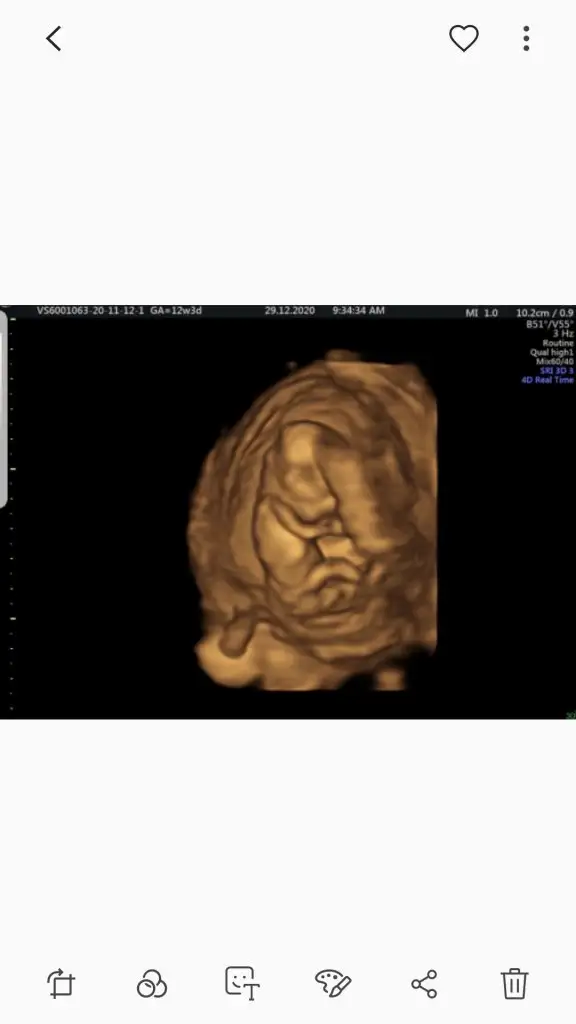

Bir de bana yorum yapar mısın? Gönderdiğim fotolar sat a göre 12+3 ultrasona göre 13+1.

Ikra meyra merhaba canım bana da yorum yapar mısın 12+3

Evet kız görünüyor